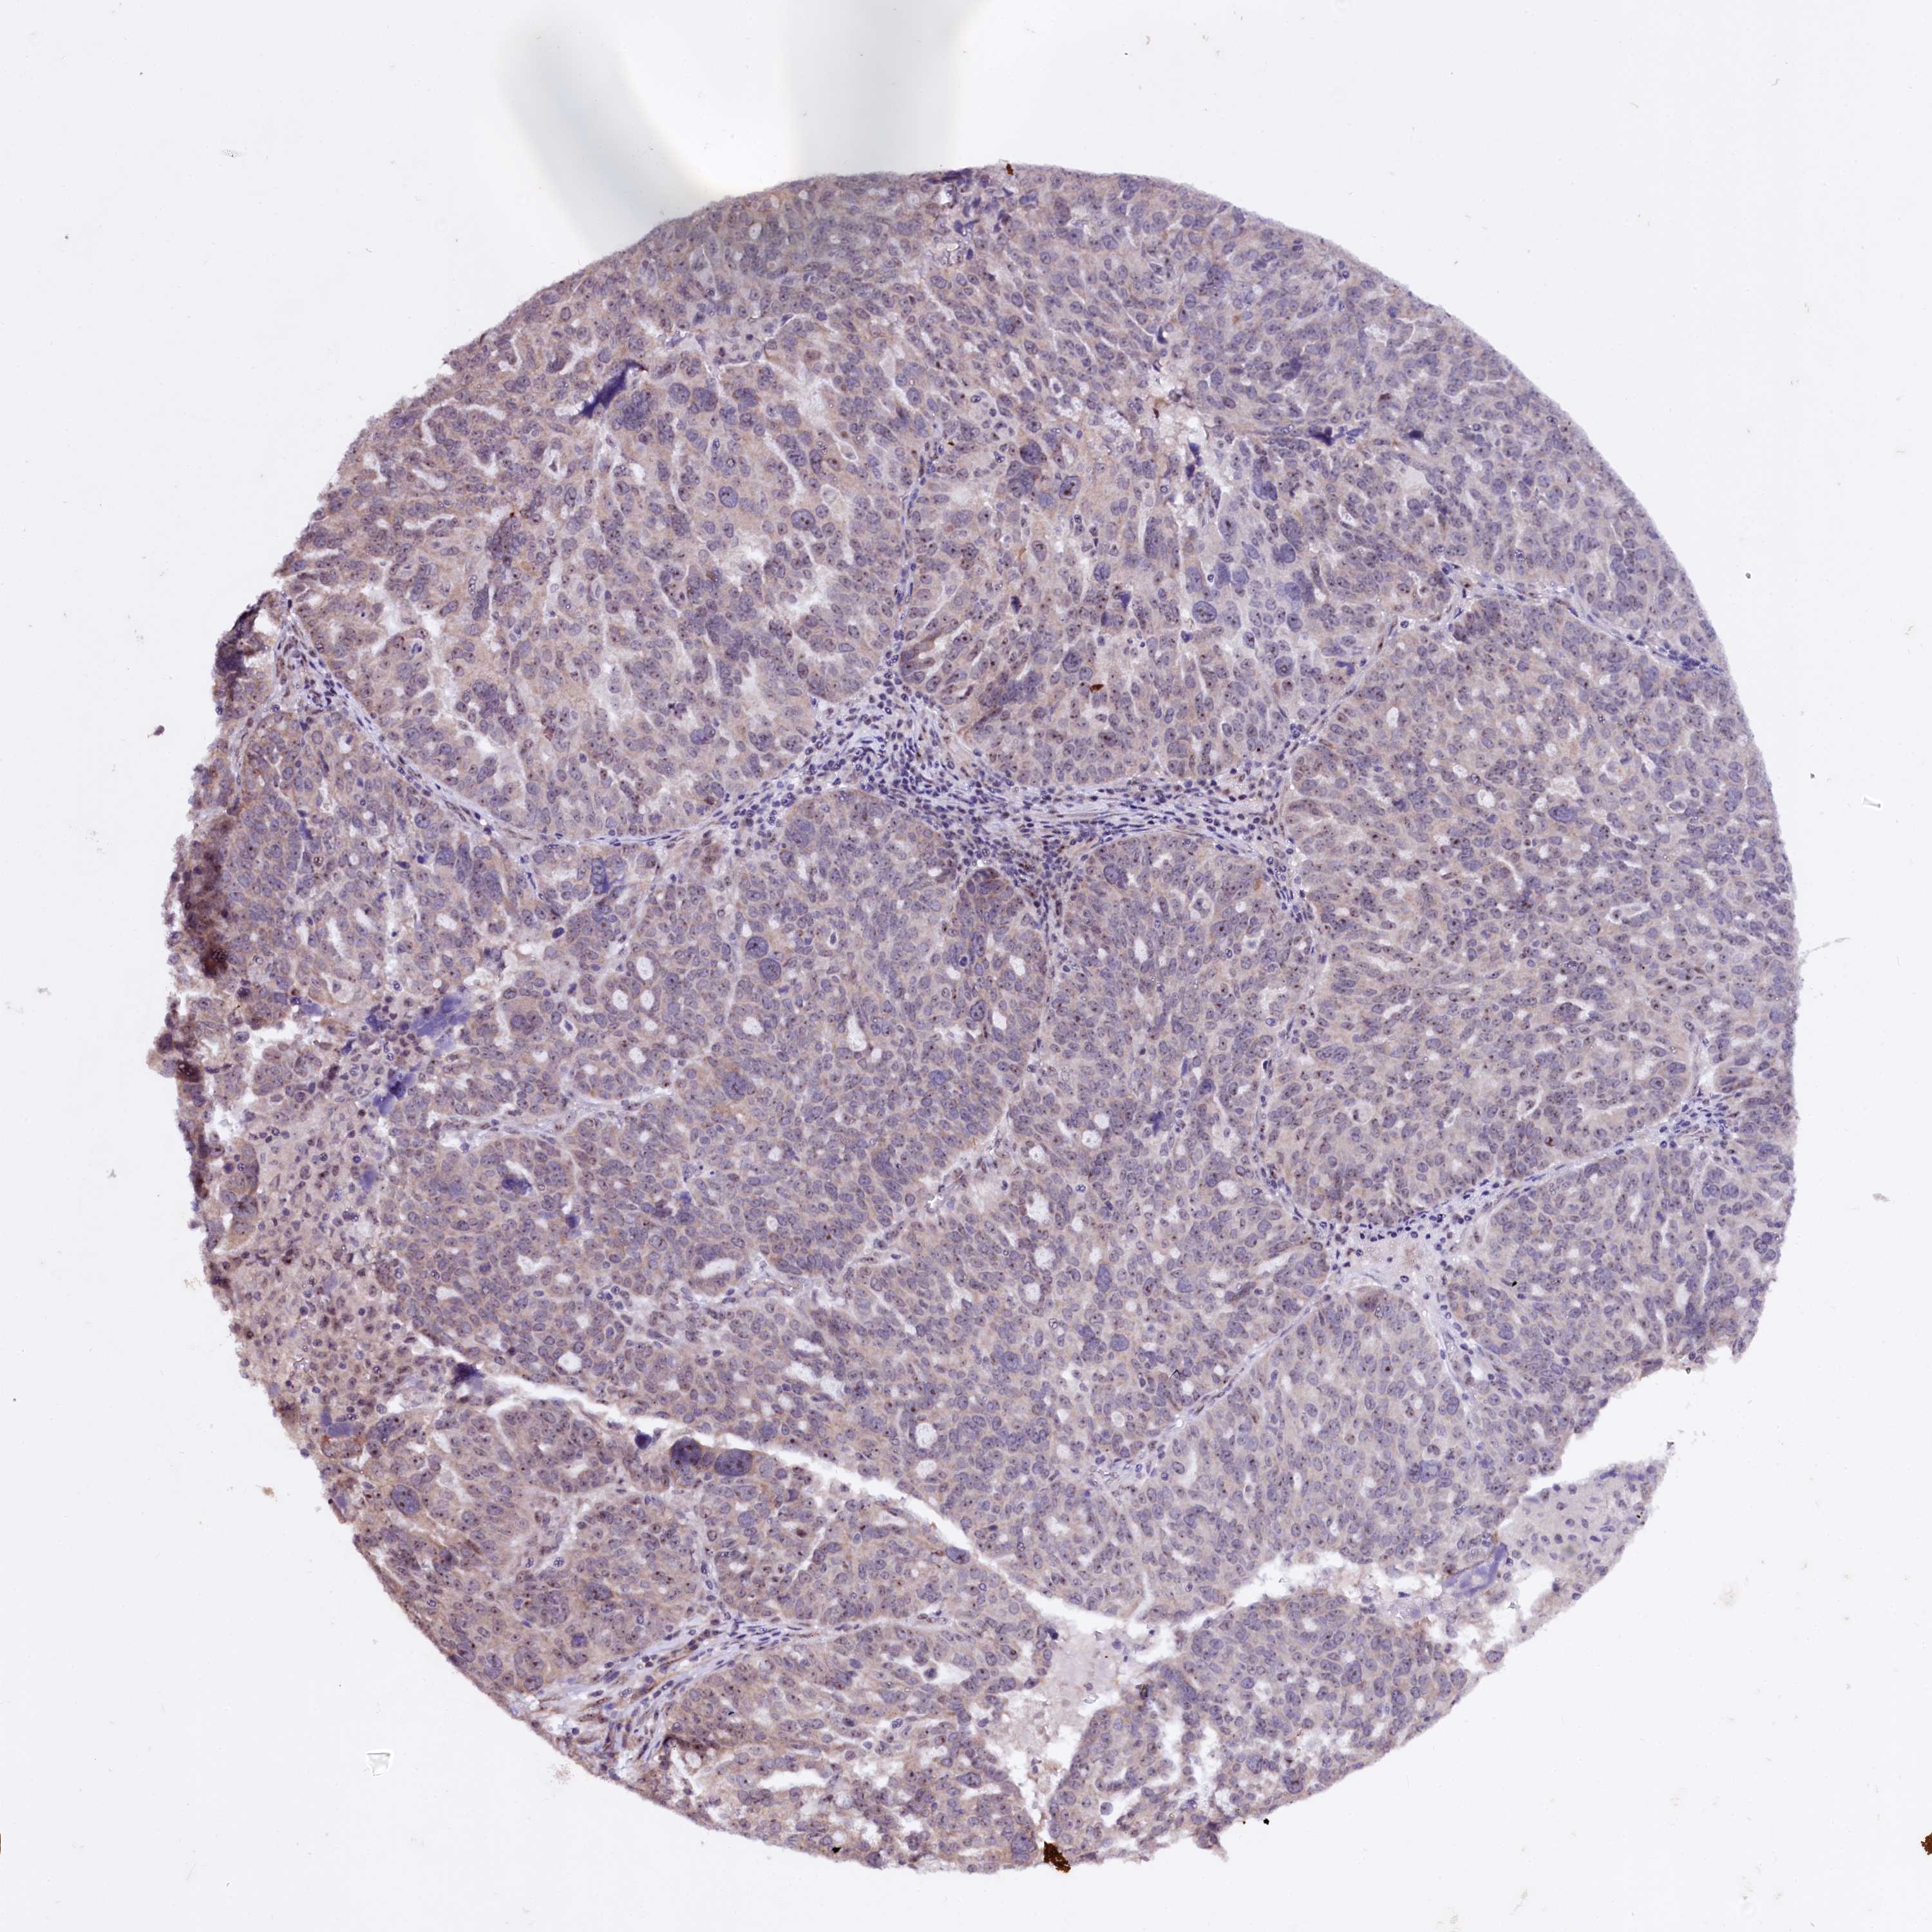

OVARIAN CANCER - Protein expressioni

A mouse-over function shows sample information and annotation data. Click on an image to view it in a full screen mode. Samples can be filtered based on level of antibody staining by selecting one or several of the following categories: high, medium, low and not detected. The assay and annotation is described here.

Note that samples used for immunohistochemistry by the Human Protein Atlas do not correspond to samples in the TCGA dataset.

Antibody stainingi

Antibody staining in the annotated cell types in the current human tissue is reported as not detected, low, medium, or high, based on conventional immunohistochemistry profiling in selected tissues. This score is based on the combination of the staining intensity and fraction of stained cells.

Each image is clickable and will lead to virtual microscopy that enables deeper exploration of all samples and also displays staining intensity scores, fraction scores and subcellular localization as well as patient and tissue information for each sample.

Antibody HPA038860

Staining

High

Medium

Low

Not detected

Intensity

Strong

Moderate

Weak

Negative

Quantity

>75%

75%-25%

<25%

None

Location

Nuclear

Cytoplasmic/membranous

Cytoplasmic/membranous,nuclear

Cystadenocarcinoma, serous, NOS

Carcinoma, endometroid

Cystadenocarcinoma, mucinous, NOS

Carcinoma, NOS